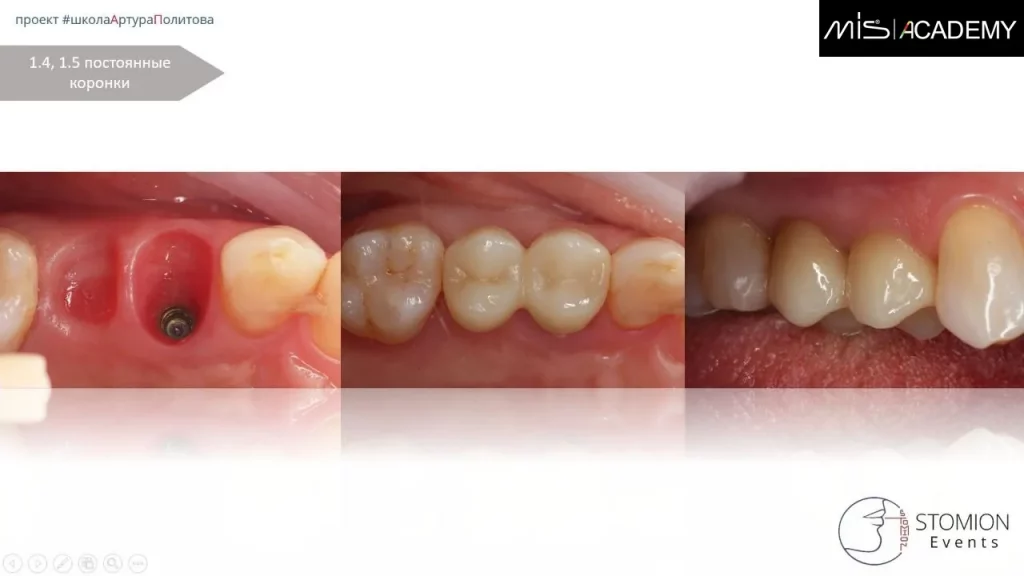

— Через 14 дней установка временной коронки.

— Через 3 месяца удаление 1.5, сгусток, колапол, ДСДТ вестибулярно, замена временной коронки 1.4 на коронку с консолью на 1.5.

— Через 6 месяцев изготовление постоянной консольной конструкции.